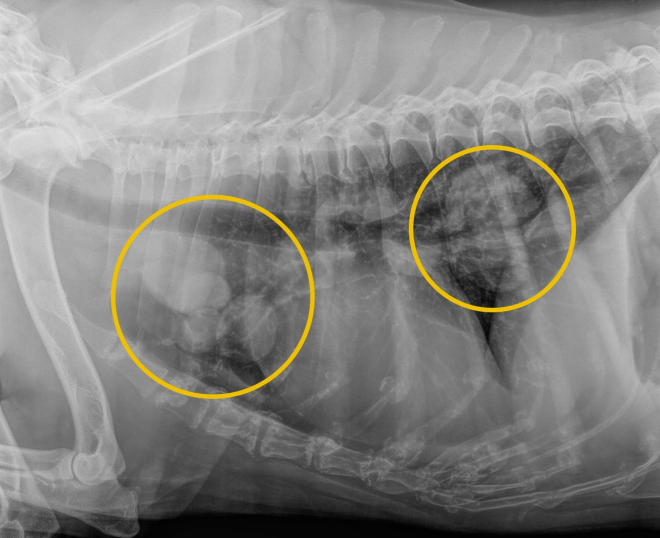

- ์ฃผ๋ก lame, ๊ด์ ๊ทผ์ฒ์ ์ข ๊ดด(mass) ๊ด์ฐฐ

- ๊ด์ ์์ธก์์ ๋ผ์ ๋ณํ๊ฐ ๋ํ๋จ - subchondral bone & cortex์ lysis, new bone production